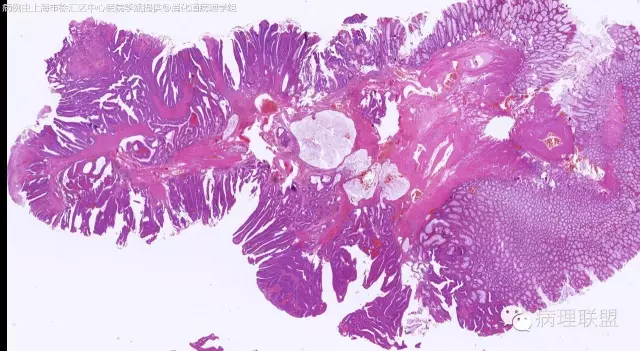

管状~绒毛状腺瘤伴低级别上皮内瘤变,黏膜下层部分腺体破裂黏液外溢伴黏液糊形成。

本例部分腺体异位到黏膜下层。

@李斌 李大夫的片子一向漂亮,有赏心悦目的感觉,必须赞一个。这例同意周大夫的意见,低级别绒毛管状腺瘤伴腺体破裂导致的黏液外溢。粘液池周围可见血管扩张淤血、含铁血黄素沉积、肉芽组织形成,提示发生过蒂扭转和出血,这常是造成假浸润、粘液溢出的原因。比较大的绒毛管状腺瘤会有分叶结构,会有比较粗大的平滑肌干,但缺少P-J息肉叶脉样从主干再分支出来的细平滑肌束。作为错构瘤性息肉的一种,P-J息肉的腺体可以分支、扩张、腺腔不规则,但没有细胞异型性,伴发异型增生时,局部出现细胞异型性但不会像这例这样齐刷刷都是异型的腺体。